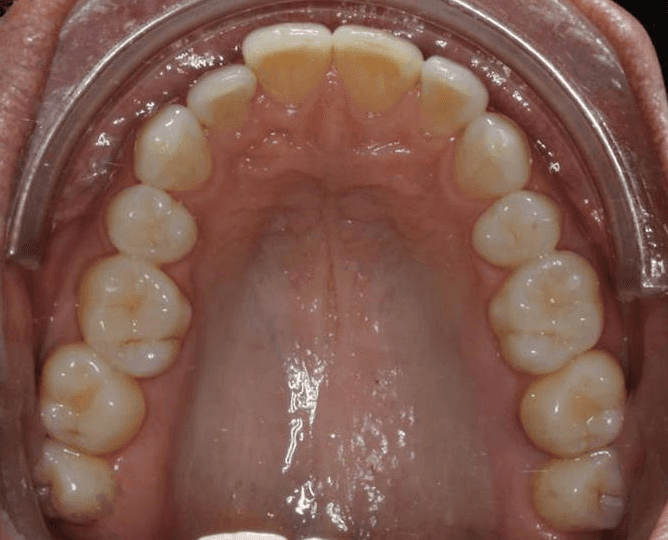

Initial treatment

INTRAORAL